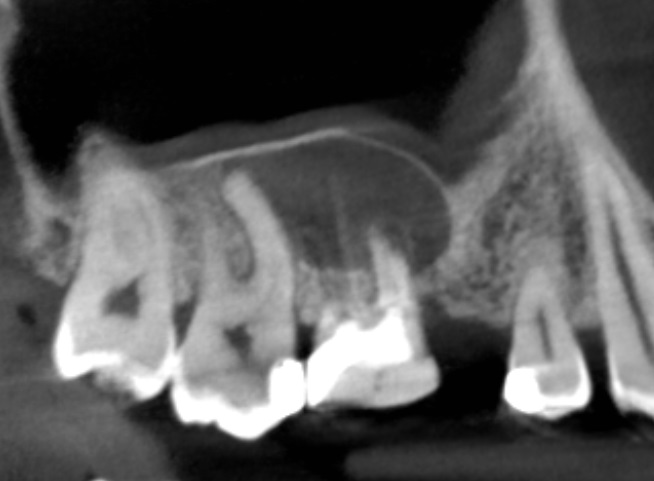

Kanały policzkowe udało się opracować i wypełnić do 1/3 wierzchołkowej, dalsze części kanałów były całkowicie zobliterowane. W trakcie opracowywania kanału podniebiennego zauważono wyciek żółtego opalizującego płynu spoza wierzchołka korzenia zęba, który po kilku minutach samoistnie ustał. Zasugerowało to obecność torbieli korzeniowej. Po zakończeniu leczenia endodontycznego wykonano zdjęcie punktowe kontrole (ryc. 2) oraz tomografię komputerową wiązki stożkowej (cone beam computed tomography – CBCT) opisywanego zęba. Jej rezultat przedstawiają ryciny 3‑6. Widzimy na nich znacznych rozmiarów torbiel korzeniową, która w toku leczenia musi zostać usunięta. Ustalono rozpoznanie ostateczne – torbiel okołowierzchołkowa. Omówiono z pacjentem jego stan i zaproponowano dalsze leczenie, na które wyraził zgodę.

Ryc. 3. CBCT – obraz zmiany w płaszczyźnie strzałkowej.